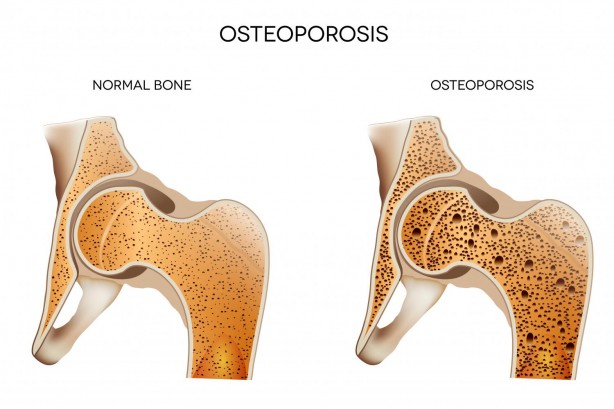

Her 3 kadının ve her 5 erkeğin 1’in görülüyor Günde sadece yarım saat ile kurtulabilirsiniz

Osteoporozu önlemenin mümkün olduğunu belirten Fizik Tedavi ve Rehabilitasyon Uzm. Dr. Öğr. Üyesi Elif Berber, “Osteoporoz önlemenin en önemli yolları D vitamini kullanmak, güneşlenmek ve kemiği güçlendirici egzersizleri uygulamaktan geçer. Yarım saatlik tempolu yürüyüşler şiddetle tavsiye edilir” dedi.